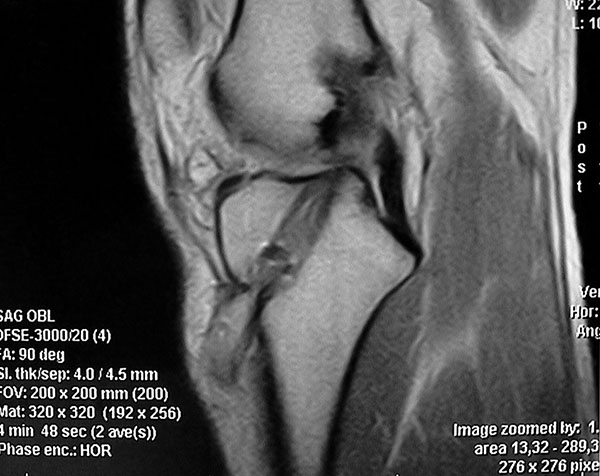

Los cuatro pacientes presentaban una rodilla estable y las radiografías no mostraban ninguna particularidad aparte de cierto ensanchamiento de los túneles. La RMI demostró una masa líquida en relación con el túnel tibial compatible con un ganglión pretibial (Fig. 3). En los exámenes de laboratorio no había signos de infección aguda.